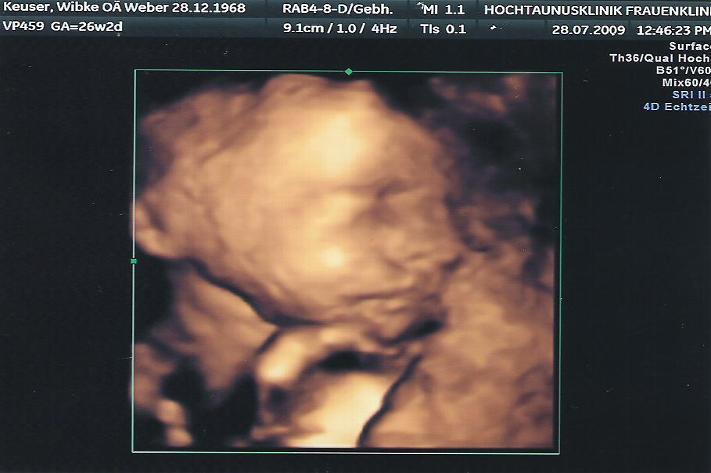

So siehst du also aus.

Endlich hat er sich mal richtig gezeigt, gesund und munter! War aber auch das letzte Mal, ....

weil er irgendwie immer etwas vor das Gesicht gehalten hat. Auch heute hält er seine Hände noch oft im Gesicht.